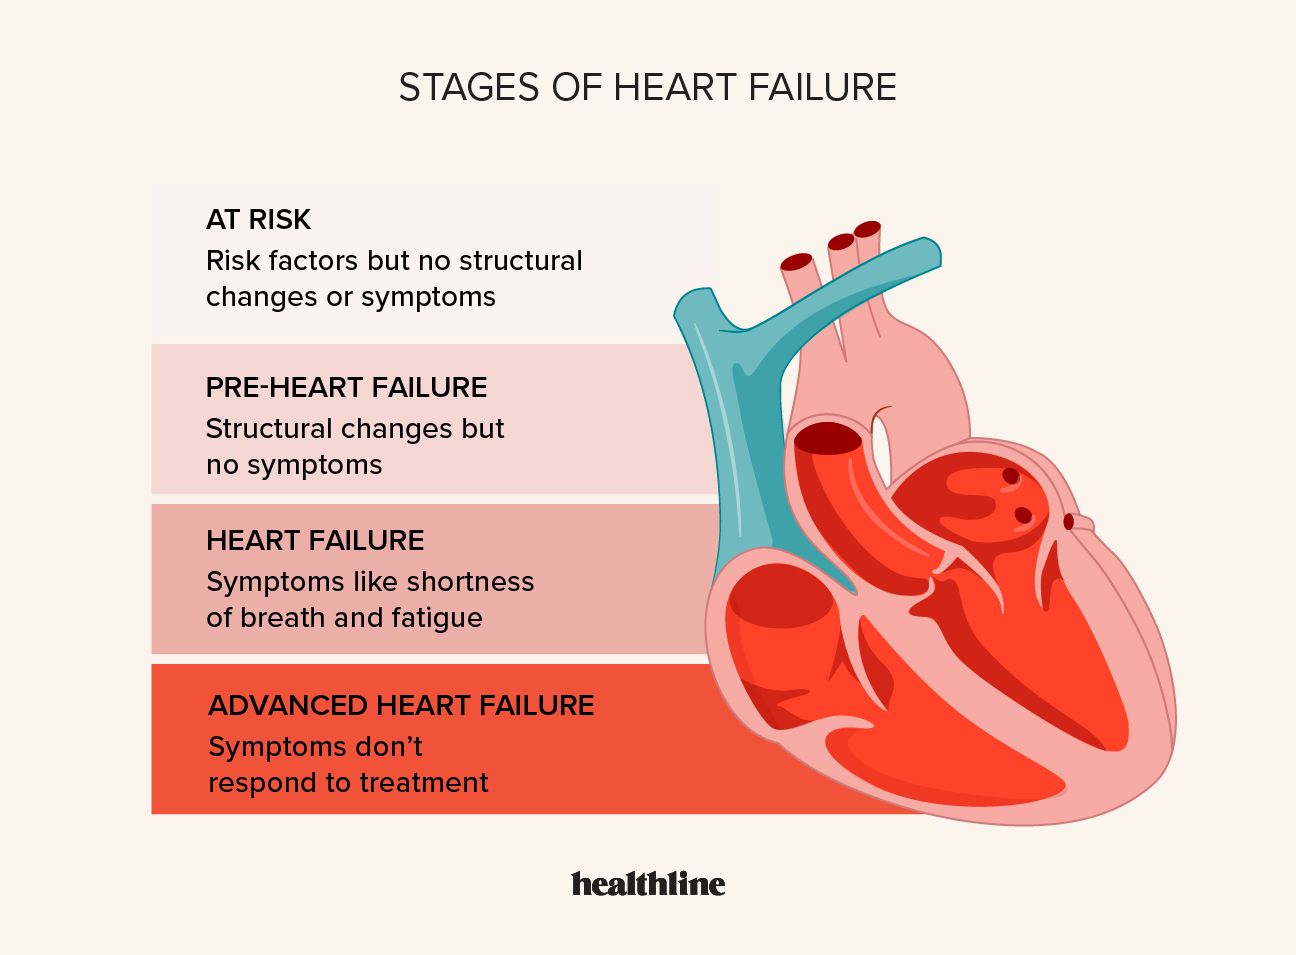

Congestive Heart Failure Stages Treatment And Outlook

Congestive Heart Failure Symptoms